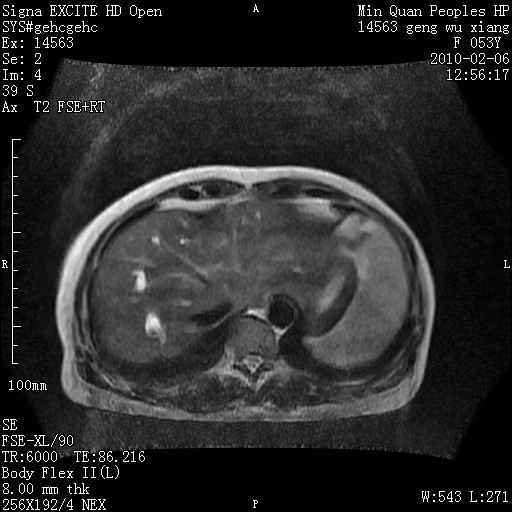

标题: MRI2762:胆道梗阻原因?

f,53y,全身黄染多日。

高位胆道梗阻 胆管癌可能性大

支持 高位胆道梗阻 胆管癌可能性大。